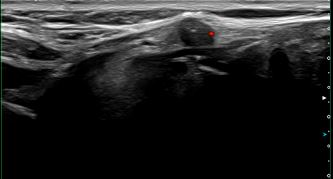

상기환자 외부검사상 갑상선 이상소견으로 추적관찰위해 내원하신 50대 중반 여성분으로

의심스러운 갑상선 좌엽 세포검사후 갑상선암으로 진단되었습니다